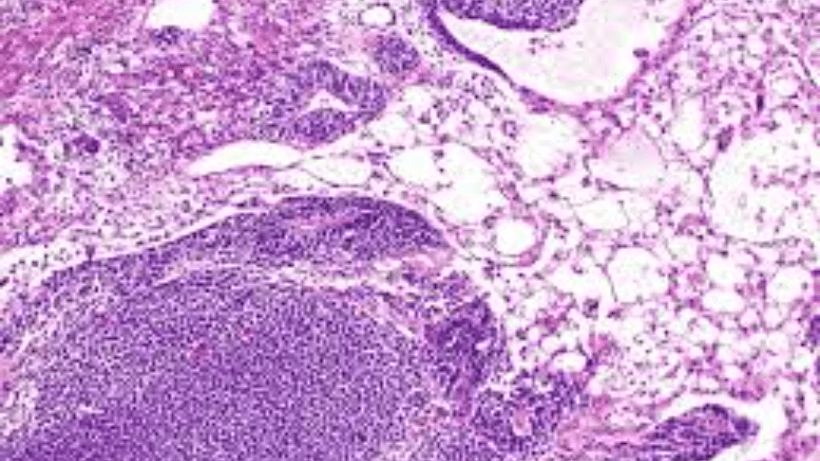

1. Dysgerminoma:

Dysgerminomas are the most common malignant germ cell tumors of the ovary. They often occur in adolescents and young women. Dysgerminomas are highly sensitive to radiation and chemotherapy, and they have a favorable prognosis when diagnosed and treated early.